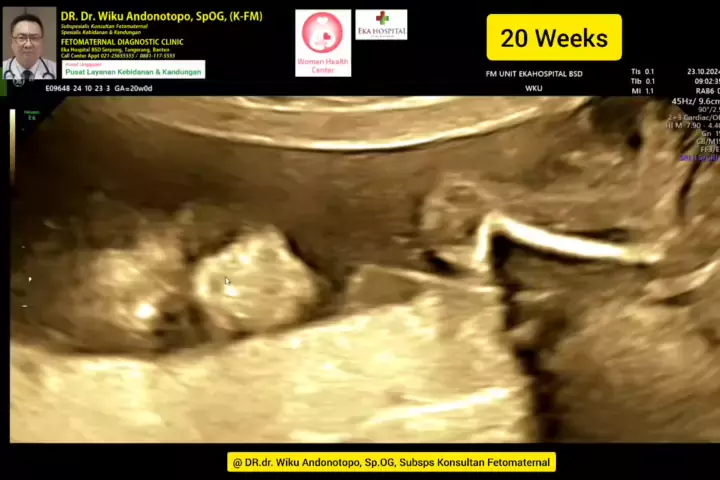

Skrining 20 weeks... #skriningkehamilan #drwikuandonotopo #drwiku_andonotopo #polikandunganekahospitalbsd #ekahospitalbsd #ekahospitalcibubur #ekahospitalpekanbaru #ekahospitalbekasi #rsiafamilypluit #grandfamilypik #usgkehamilansehat #usgkehamilan #usg4d #usg4dimensi #fetomaternal #usgfetomaternal #konsultanfetomaternal #fetomaternalpontianak #fetomaternalekahospitalbsd #fetomaternaljakarta #fetomaternalserpong #fetomaternaltangerang #fetomaternalmedan #fetomaternalpalembang #fetomaternalpadan...